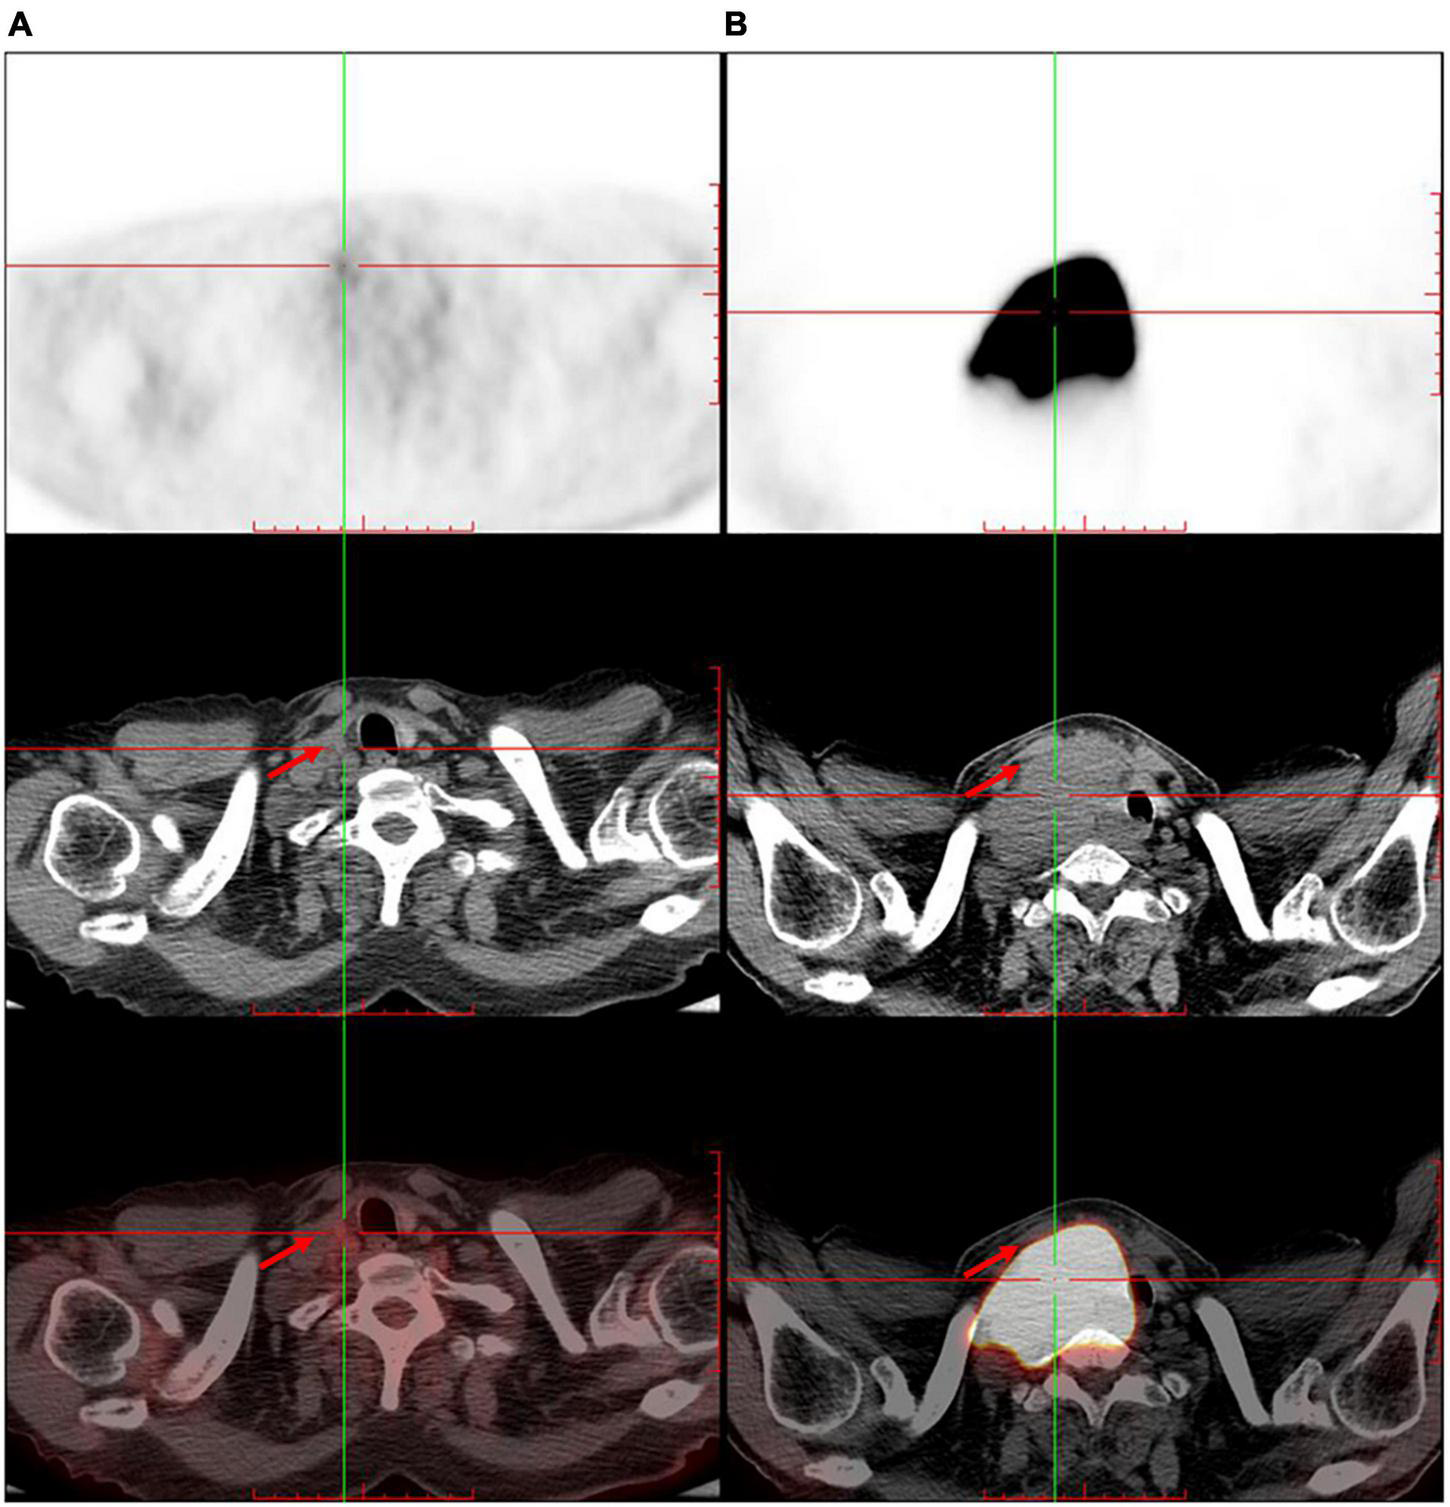

The patient was referred to the hematology department for further treatment. After the assessment of the involved site, he was diagnosed as having diffuse large B-cell lymphoma (Ann Arbor stage, IV; International Prognostic index, 2) and secondary carotid sinus syndrome (CSS). He received immunochemotherapy, i.e., rituximab (600 mg), plus cyclophosphamide (1.2 g), doxorubicin (60 mg), vincristine (4 mg), and prednisone (100 mg/day × 5 day) (R-CHOP). After four cycles of R-CHOP immunochemotherapy, PET/CT revealed that the original large mass in the neck had disappeared (Figure 3). The patient no longer complained of either syncope or pain from the post-auricular and occipital regions. Choking when eating was also relieved (Table 1).

FIGURE 3

The trunk positron emission tomography/computed tomography shows significant shrinkage of the original large mass in the right neck after four cycles of immunochemotherapy. (A) After immunochemotherapy for four cycles. (B) Before the immunochemotherapy. Red arrow indicates the tumor.